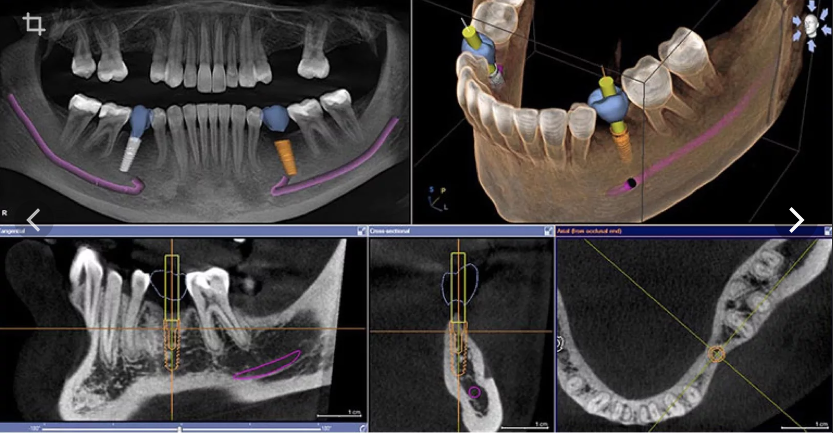

Продвинутый курс: Навигационная имплантология: цифровые протоколы от планирования до хирургии.

Андрей Добрынин